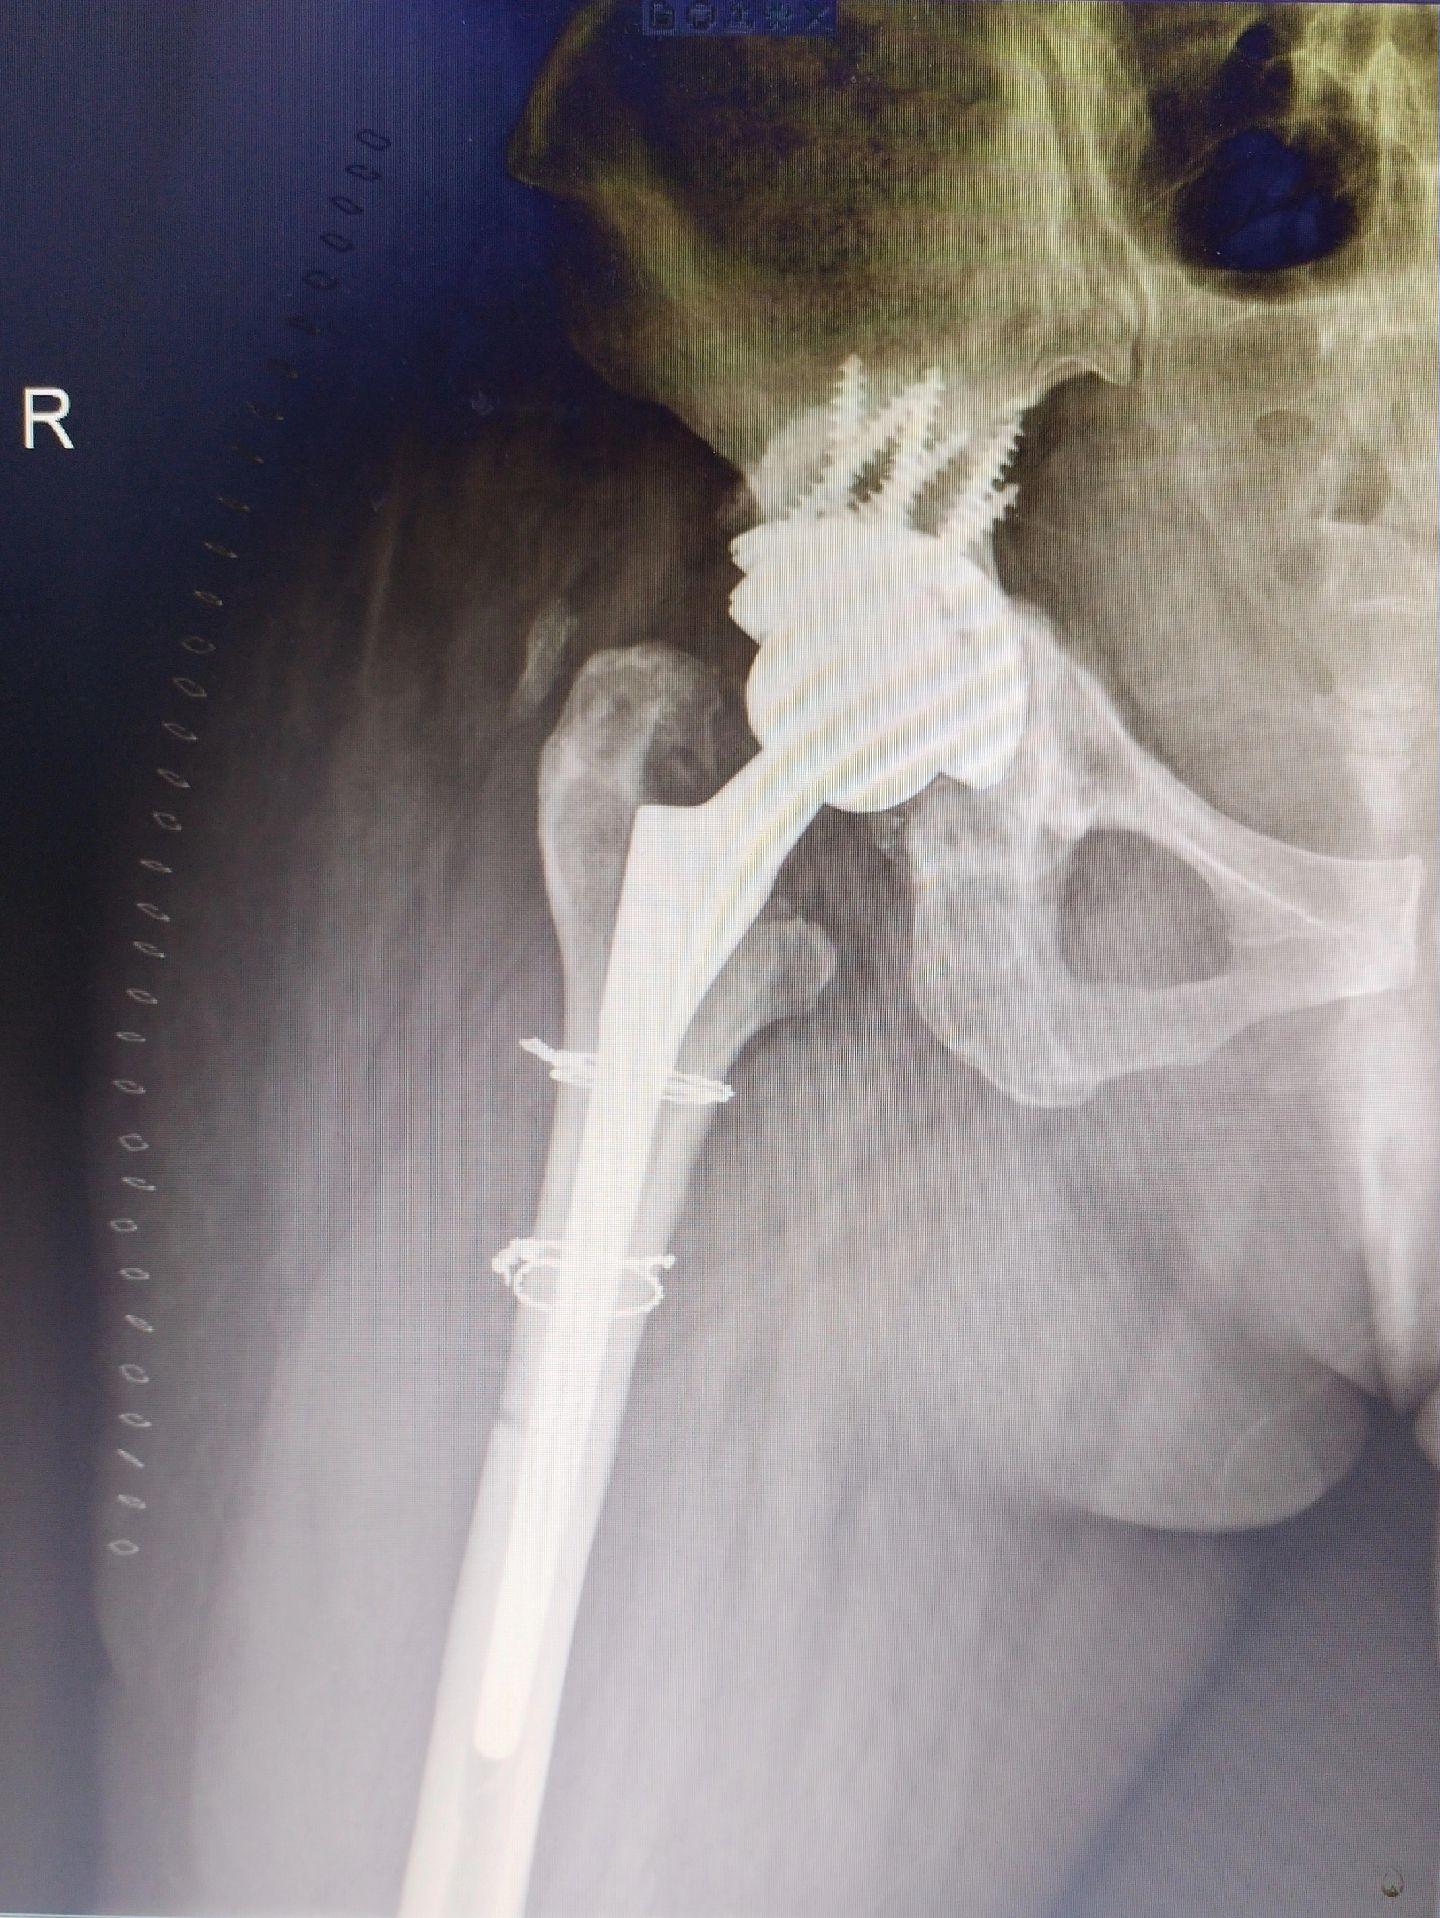

髋关节翻修术。髋关节置换术后假体磨损导致松动,一期翻修,只要重建的牢固,一样可以两天下床走路。愿每一个病人都能快速康复🌹关节置换

髋关节翻修术。髋关节置换术后假体磨损导致松动,一期翻修,只要重建的牢固,一样可以两天下床走路。愿每一个病人都能快速康复🌹